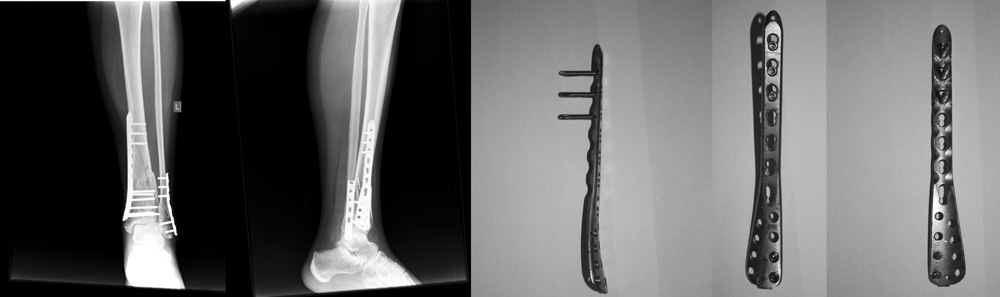

МОС голени год назад (март 2013). Удаление ровно через год (март 2014).

Столкнулся с тем, что удаление пластины с малоберцовой кости произошло

без каких-либо проблем, а вот с большеберцовой кости не удалось

выкрутить 5 винтов (2 снизу и 3 сверху). Только трепанация кости в зоне

фиксации винтов послужила возможностью для удаления пластины.

Представитель производителя комментирует ситуацию "как обычную" и

встречающуюся не чаще, чем у других производителей (Synthes, koenigsegg)

в виде типичной "холодной пайки", а так как шаблоны фиксаторов построены

аналогично вышесказанным производителям, то и последствия достаточно

прогнозированы. По рекомендациях удаления вместо трепанации кости было

предложено высверливание головок винтов из пластины.